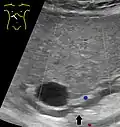

Choledocholithiasis (stones in common bile duct) is one of the complications of cholelithiasis (gallstones), so the initial step is to confirm the diagnosis of cholelithiasis. Patients with cholelithiasis typically present with pain in the right-upper quadrant of the abdomen with the associated symptoms of nausea and vomiting, especially after a fatty meal. The physician can confirm the diagnosis of cholelithiasis with an abdominal ultrasound that shows the ultrasonic shadows of the stones in the gallbladder.